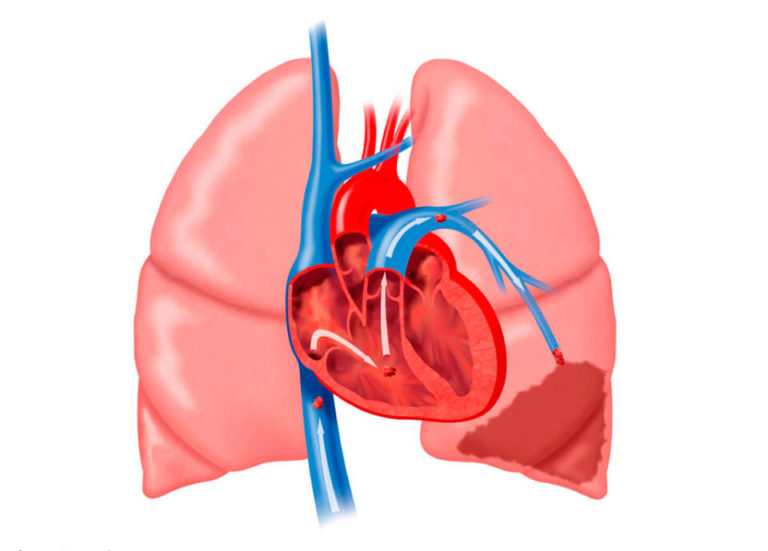

Остановка движения тромба может происходить в крупных сосудах, которые переносят жидкую соединительную ткань от легких к сердцу, а также в их ответвлениях. Последствия зависят от числа «плавающих» частиц и их размеров. Чем больше тромбы, тем выше вероятность полного перекрытия жизненно важных артерий.

Тромбы могут образовываться не только в нижних конечностях и области таза, но и в правом предсердии, а также в верхних конечностях, хотя такие случаи встречаются реже. Механизм прост: при повреждении верхнего слоя сосудов открывается следующий, что способствует более быстрому свертыванию крови, и к этому участку присоединяются другие частицы.

- массивная – затрагивает две трети легочных ветвей (вызывает болевые ощущения в крупных артериях и стволе), приводит к снижению артериального давления и может вызвать шоковое состояние;

- субмассивная – поражает одну треть сосудистой сети (затрагивает отдельные сегменты органов дыхания), может повлиять на правый желудочек сердца и вызвать нарушения в работе миокарда;

- немассивная – проявляется поражением менее одной трети всей дыхательной структуры (речь идет о более мелких артериях), сопровождается минимальными симптомами или их полным отсутствием, может привести к инфаркту одного из органов дыхания.